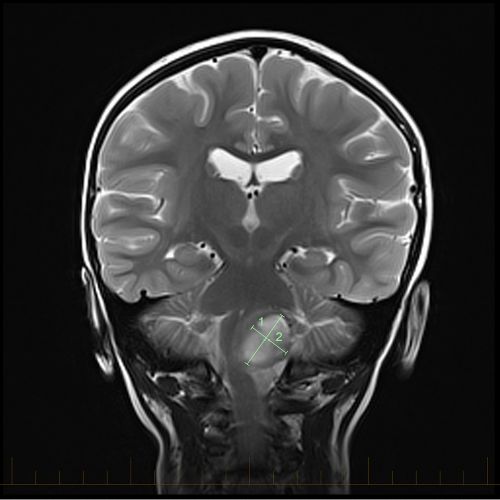

X Ray Multiple Part Of Child S Body Multiple Disease Stroke Brain Tumor Rheumatoid Arthritis Sinusitis Gouty Arthritis Etc Skull Chest Lung Heart Spine Arm Hand